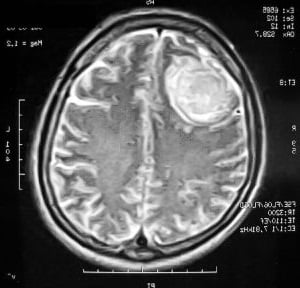

Наиболее информативными способами диагностики при менингиоме остаются следующие:

- МРТ — магнитно-резонансная томография является абсолютно безопасной, поэтому часто используется для проверки состояния пациента на ранних дооперационных стадиях и в период послеоперационного восстановления. МРТ помогает распознать рецидив заболевания, а также определить наличие опухоли при объеме всего в несколько миллиметров.

- Компьютерная томография — обследование проводится с контрастным усилением. КТ признаки указывают на наличие опухоли, а также помогают выявить природу новообразования, не прибегая к дополнительным диагностическим процедурам. Злокачественная опухоль имеет тенденцию накапливать контраст в своих тканях, что и становится очевидным на снимке КТ.